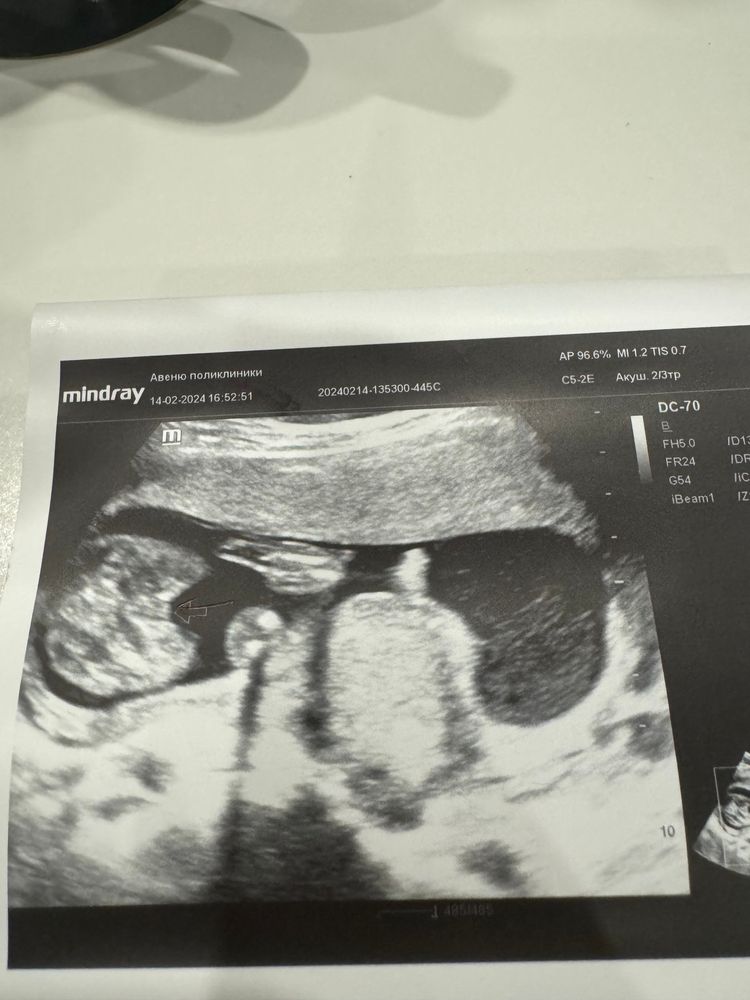

К сожалению на таком сроке не делали узи. Есть фото немного более позднего периода. Если память не подводит была 20-21 неделя. Зато сказали 100 % мальчик. А выглядит это так:

10.04.2017